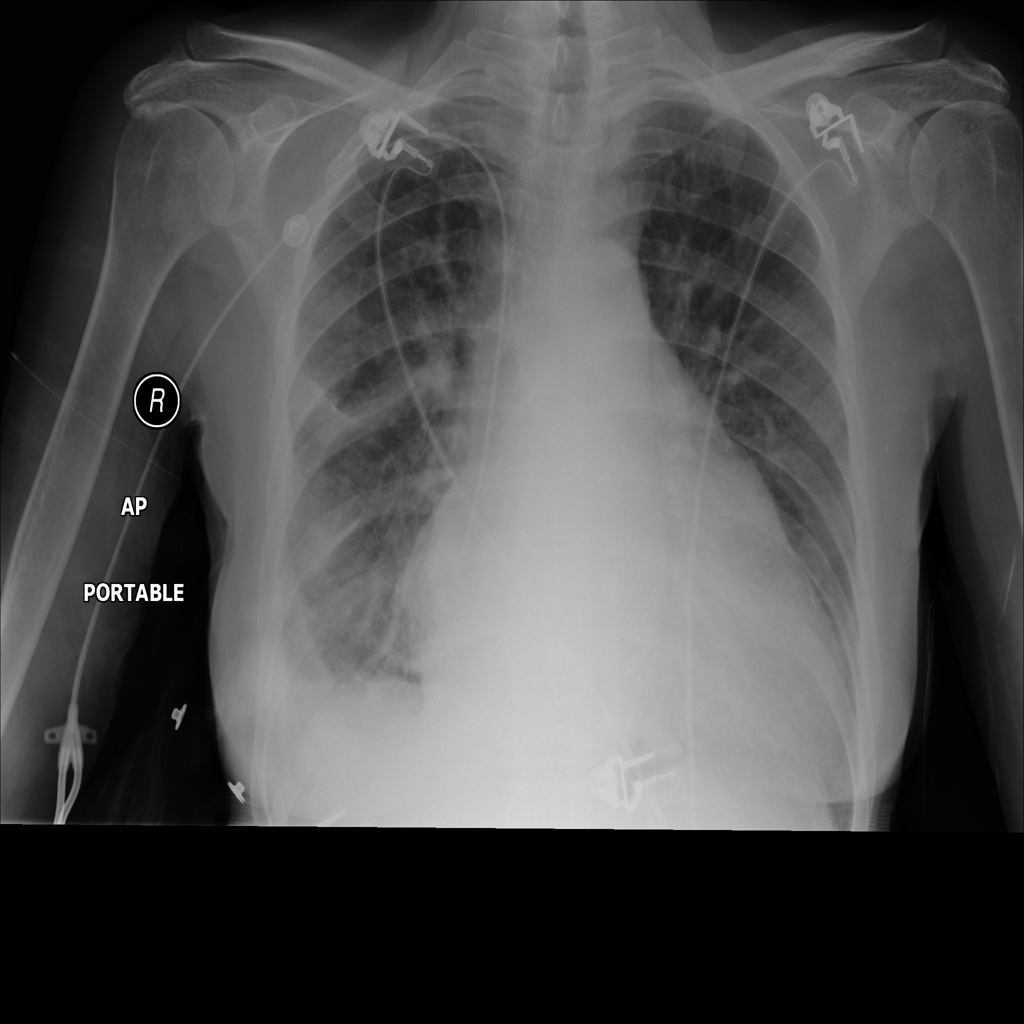

PAT-E81B · IMG-000Effusion

PAT-E81B · IMG-000

PA